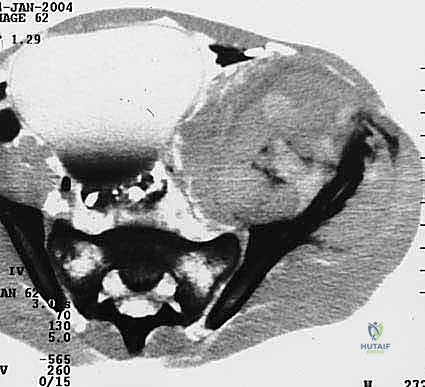

- التصوير المقطعي المحوسب (CT Scan): يقدم صوراً ثلاثية الأبعاد تُظهر بدقة متناهية مدى تدمير القشرة العظمية، وهو الفحص الأهم للتخطيط الجراحي وتحديد خطر حدوث الكسور المرضية.

3. المرض المتقدم محلياً (Local Progression)

إذا استمر الورم في النمو وتدمير العظم رغم خضوع المريض للعلاج الإشعاعي والكيميائي، فإن الاستئصال الجراحي للكتلة الورمية الكبيرة يصبح ضرورياً لإنقاذ الطرف السفلي ومنع المضاعفات العصبية والوعائية.

3. الاستئصال الواسع وإعادة البناء بالمفاصل المخصصة (Wide Resection & Megaprostheses)

في الحالات التي يكون فيها الورم من